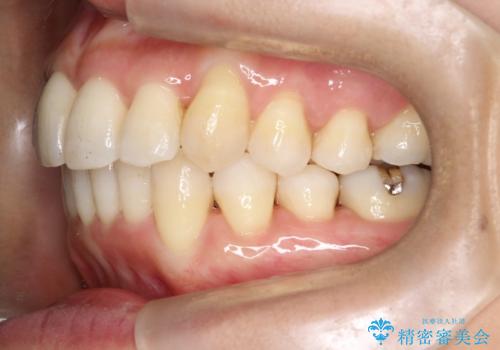

重度のガタガタのインビザラインによる非抜歯矯正

しっかりとマウスピースを使用していただけたので、順調に治療を終えることができました。